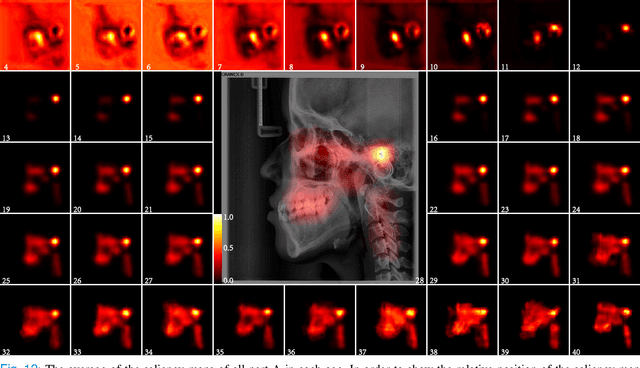

The traditional manual age estimation method is crucial labor based on many kinds of the X-Ray image. Some current studies have shown that lateral cephalometric(LC) images can be used to estimate age. However, these methods are based on manually measuring some image features and making age estimates based on experience or scoring. Therefore, these methods are time-consuming and labor-intensive, and the effect will be affected by subjective opinions. In this work, we propose a saliency map-enhanced age estimation method, which can automatically perform age estimation based on LC images. Meanwhile, it can also show the importance of each region in the image for age estimation, which undoubtedly increases the method's Interpretability. Our method was tested on 3014 LC images from 4 to 40 years old. The MEA of the experimental result is 1.250, which is less than the result of the state-of-the-art benchmark because it performs significantly better in the age group with fewer data. Besides, our model is trained in each area with a high contribution to age estimation in LC images, so the effect of these different areas on the age estimation task was verified. Consequently, we conclude that the proposed saliency map enhancements chronological age estimation method of lateral cephalometric radiographs can work well in chronological age estimation task, especially when the amount of data is small. Besides, compared with traditional deep learning, our method is also interpretable.